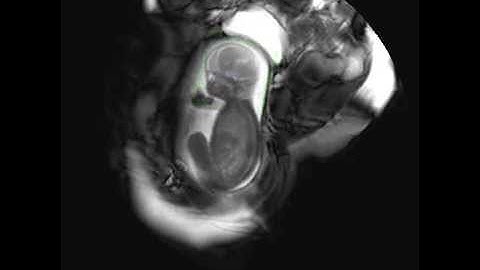

Kevin Keraudren: Localising organs of the fetus in MRI data using Python